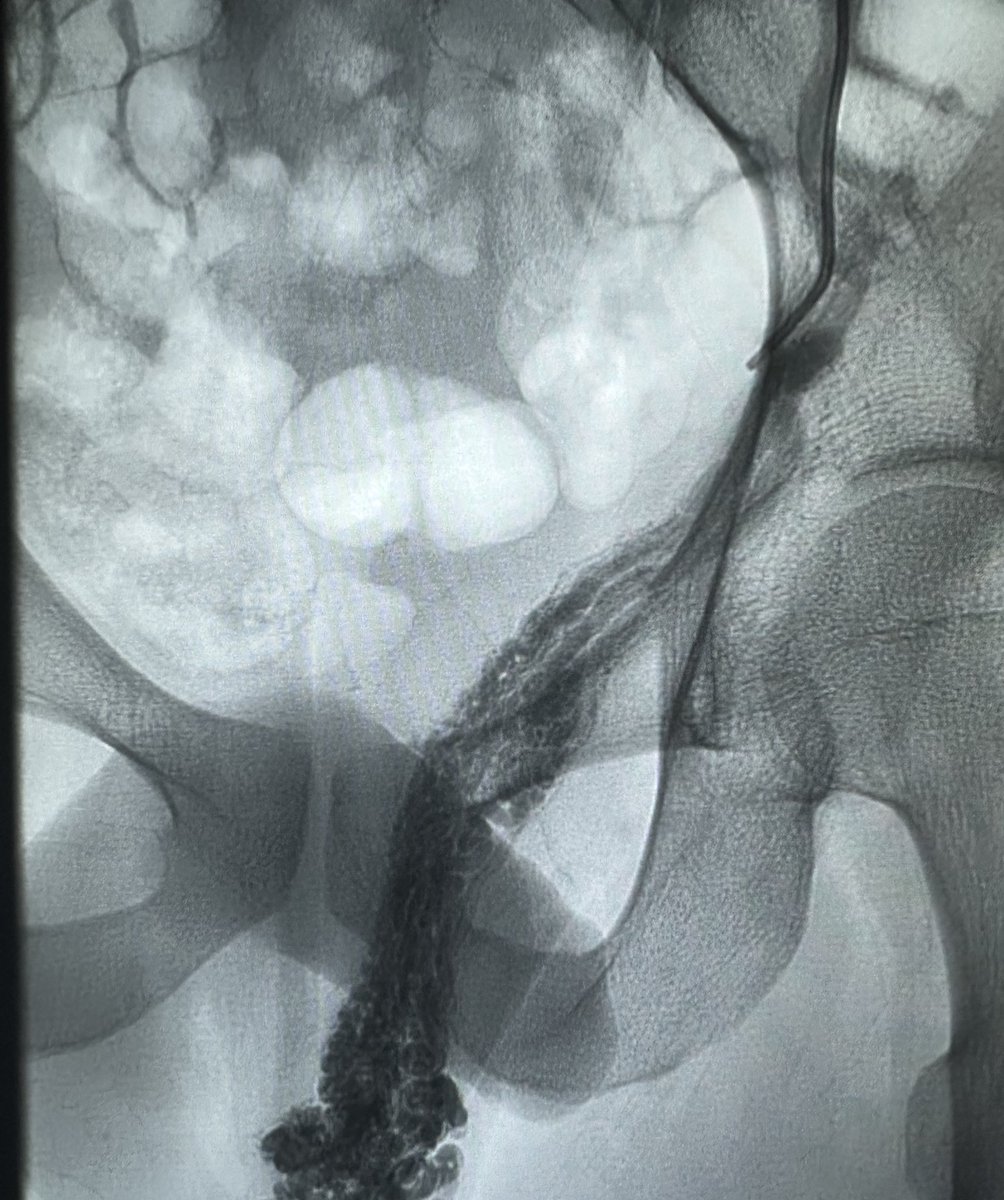

طريقة تغلغل الصمغ الطبي في علاج الأوردة المغذية لدوالي الخصية بالقسطرة. اغلاق جميع الأوردة بدون المساس بالقنوات الليمفاوية (فلا يحصل قيلة مائية) ولا الشعيرات الشريانية الدقيقة (فلا يحصل ضمور) القسطرة والأشعة التداخلية اثبتت بالابحاث افضليتها على الجراحة من كل النواحي

علاج دوالي الخصية بالأشعة التداخلية ، العلاج بالصمغ الطبي يعتبر أفضل وأحدث علاج. يتم إغلاق الدوالي والأوردة بدقة دون التعرض للشرايين والقنوات الليمفاوية الدقيقة. مثال لمريض لديه ما يفوق عن ٤٠ وريد ، لا يمكن ربطها جميعاً جراحياً. بالقسطرة؟ انتهينا من الجهتين خلال اقل من ١٠ دقائق.

لولا وجود الندبة الجراحية لما صدّقت. مريض سبق وأن عمل عملية دوالي خصية مجهرية (مايكروسكوب) وبالطبع لم يتم علاجها بالشكل الصحيح. الأشعة التداخلية وضحت دوالي مهولة من ناحية العدد والحجم… لماذا يتعرض المريض للعملية بمخاطرها (ضمور صامت بنسبة ١ من كل ١٤٠ مريض أو قيلة مزمنة بنسبة ١-٢